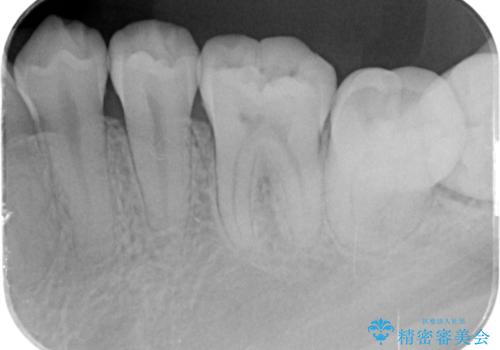

歯冠長延長術をおこなったアプローチの難しい虫歯治療

- 親知らずの抜歯を希望され来院されましたが手前の大臼歯2本に虫歯が認められ、治療が必要な状態でした。

クラウン形態にするには歯の高さが足りず設計できないため、親知らずの抜歯と共に歯周外科を同時に行うことで安定した歯周組織を獲得しセラミック治療を行う治療計画としました。

歯冠長の延長を行ったことで、安定したクラウン治療を行うことができました。